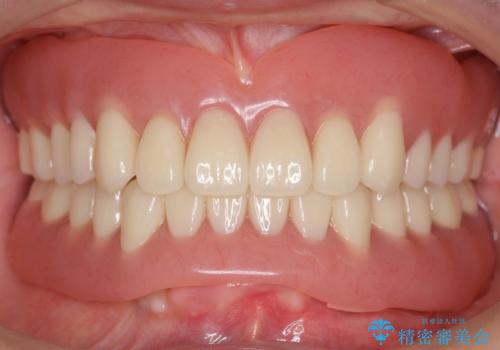

- 他院にて入れ歯を入れたが全体的に左に傾いており、咬みにくく、見た目も気になるといらっしゃった方の症例です。

診査の結果、虫歯が進行し保存できない歯が多かったため抜歯し、磁性アタッチメントを用いたインプラントオーバーデンチャーによる咬合及び見た目の改善を行いました。